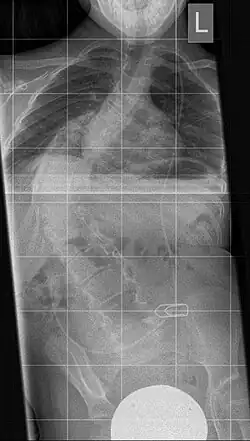

Das Instrumentarium wird eingesetzt, um bei einer schweren Thoraxdeformität einen zu kleinen oder zu schmalen Rippenthorax aufzuweiten und aufzurichten. Es besteht aus einer ausziehbaren „Titanrippe“ in gebogener Form mit mehreren Löchern in Reihe zur Fixierung in der gewünschten Länge. Nach jeweils 6 Monaten kann eine Verlängerung operativ erfolgen. Die Fixierung erfolgt zwischen zwei Rippen oder zwischen einer Rippe und dem Beckenkamm. Dadurch erfolgt eine indirekte Aufrichtung der deformierten Wirbelsäule und damit ergibt sich eine Volumenzunahme des Rippenthorax mitsamt der Lunge.